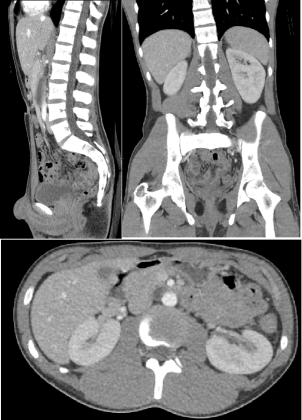

- Computed Tomography (CT): CT scans use a series of X-ray images taken from different angles to create cross-sectional images of the body. They provide detailed views of bones, soft tissues, and organs and are useful for diagnosing conditions such as tumours, infections, trauma, and vascular diseases.